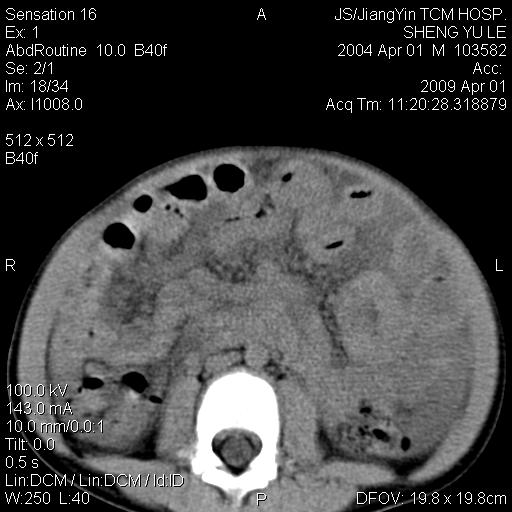

m,5岁。尿痛尿频数天。既往无病史。ct平扫腹盆腔积液。膀胱壁明显增厚。另可见心包增厚。wbc5万,骨髓穿等结果。请指教。

膀胱影像表现结合临床应该是急性膀胱炎症,但为什么有腹水呢?双肾输尿管无扩张,泌尿系压力应该不大不至于引起尿外渗,应该是腹膜感染引起的,但楼主没有提及相关症状,腹膜及膀胱结核?患者白细胞5万(结核不至于这么高啊),脾脏增大,是不是有白血病?进一步检查。。

综合观察分析考虑恶性病变

腹水,膀胱壁增厚,wbc5万,结合临床,支持感染性疾病---感染性腹膜炎、腹水,急性膀胱炎,败血症。期待结果。